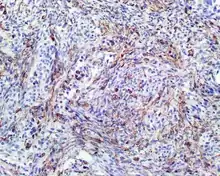

| A high-power view of a hematoxylin- and eosin-stained slide showing respiratory epithelial inclusions within a spindled cell neoplasm showing characteristics of a biphenotypic sinonasal sarcoma | |

- Infiltrative, highly cellular spindled cell neoplasm is poorly circumscribed and unencapsulated. Bone destruction or invasion is common. The cells show medium to long fascicles (nerve fibers), with a herringbone pattern. The cells are remarkably uniform with elongated nuclei. Delicate strands of intercellular collagen without ropy or dense deposition are seen. A very characteristic concurrent surface-type respiratory epithelial proliferation is found from the surface or in small cystic spaces around the cancer cells, often forming glands. The background may have a rich vascularity and usually has a small number of scattered lymphocytes. Extra growths or mitoses are rare, while necrosis, ulceration, and hemorrhage are usually absent.